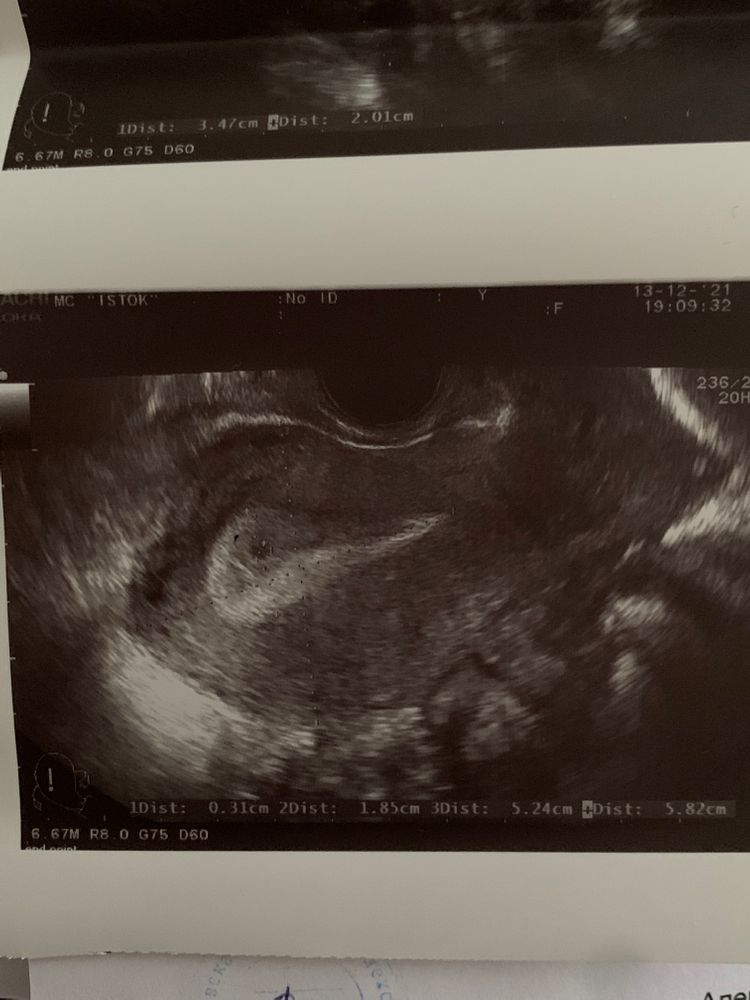

УЗИ ииииии?

На узи что то есть а тесты до сих пор отрицательные? Обычно на раннем сроке наоборот сначала тесты полосатят, потом на узи ПЯ появляется, при хгч выше 1000 и уже при ярких тестах. Не бывает Б при отрицательном ХГЧ

Mama Sveta, мне сама врач сказала, что только имплантация произошла. Это же ещё не эмбрион. Хориона нет. А именно хорион вырабатывает ХГЧ

Malinka, вы не правы, плодное яйцо на УЗИ можно увидеть от ХГЧ 1000 МЕ/мл. А за счёт чего ещё п/я имплантируется в эндометрий?

Malinka, когда ПЯ имплантируется, начинает вырабатываться хгч, и на этом этапе ПЯ настолько крохотное, что его ни одно узи не уловит. А вот когда хгч уже от 1000, пя видно. Во всяком случае хгч должен быть +. Но пускай вы и ваш узист окажетесь правы. От души желаю 🍀

Поздравляю! Пусть бусинка развивается!!! 🤗🤗🤗 Мне тоже только точку нашли сразу, боялись вБ, 10 дней были адом... боялась сильно нервничать... и не нервничать невозможно... а через 10 дней мой малыш уже хорошо был виден и билось сердечко... 🥰🥰🥰

поздравляю!))))) блин, а я везде читала, что нереально что то увидеть, если ХГЧ меньше 1000, а при таких показателях там все тесты давно полосатые как минимум) как так то?) вы тесты делали до этого?)